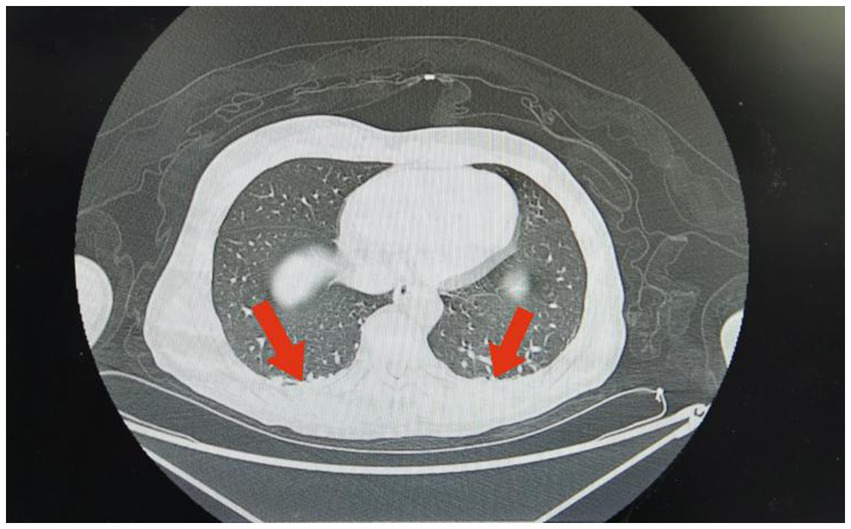

Figure 2

Imaging findings in Case 1: Chest CT shows a small area of inflammation or exudation in the left lung.

Case 1 was a 51-year-old man with no previous health issues. On admission on February 7, 2025, he presented with weak breathing and loss of consciousness. Physical examination showed a temperature of 36.5 °C, heart rate of 62 beats/min, respiratory rate of 21 breaths/min, blood pressure of 118/75 mmHg, and SpO2 of 99%, revealed a state of drug-induced sedation and tracheal intubation, with no significant abnormalities in other organ systems. Admission diagnosis: Acute poisoning; Asphyxiating gas poisoning. Laboratory and imaging test results are shown in Tables 1, 2 and Figure 2. He was treated with a combination of propofol and dexmedetomidine for sedation; betamethasone to control pulmonary inflammation; danshen polyphenols for cardiovascular protection; and mecobalamin and vitamin B1 for nerve nutrition. Continuous electrocardiogram monitoring was maintained throughout the hospital stay. During the hospitalization, respiratory indicators remained stable, and he was assessed as meeting the criteria for tracheal intubation removal. He transitioned from invasive ventilation with tracheal intubation to low-flow oxygen inhalation and successfully had the tracheal intubation removed on February 9, 2025. The patient’s overall condition was good, and he was discharged on February 14, 2025. A follow-up visit at our hospital on February 22, 2025, showed no significant abnormalities. Telephone follow-up indicated a good prognosis for the patient.